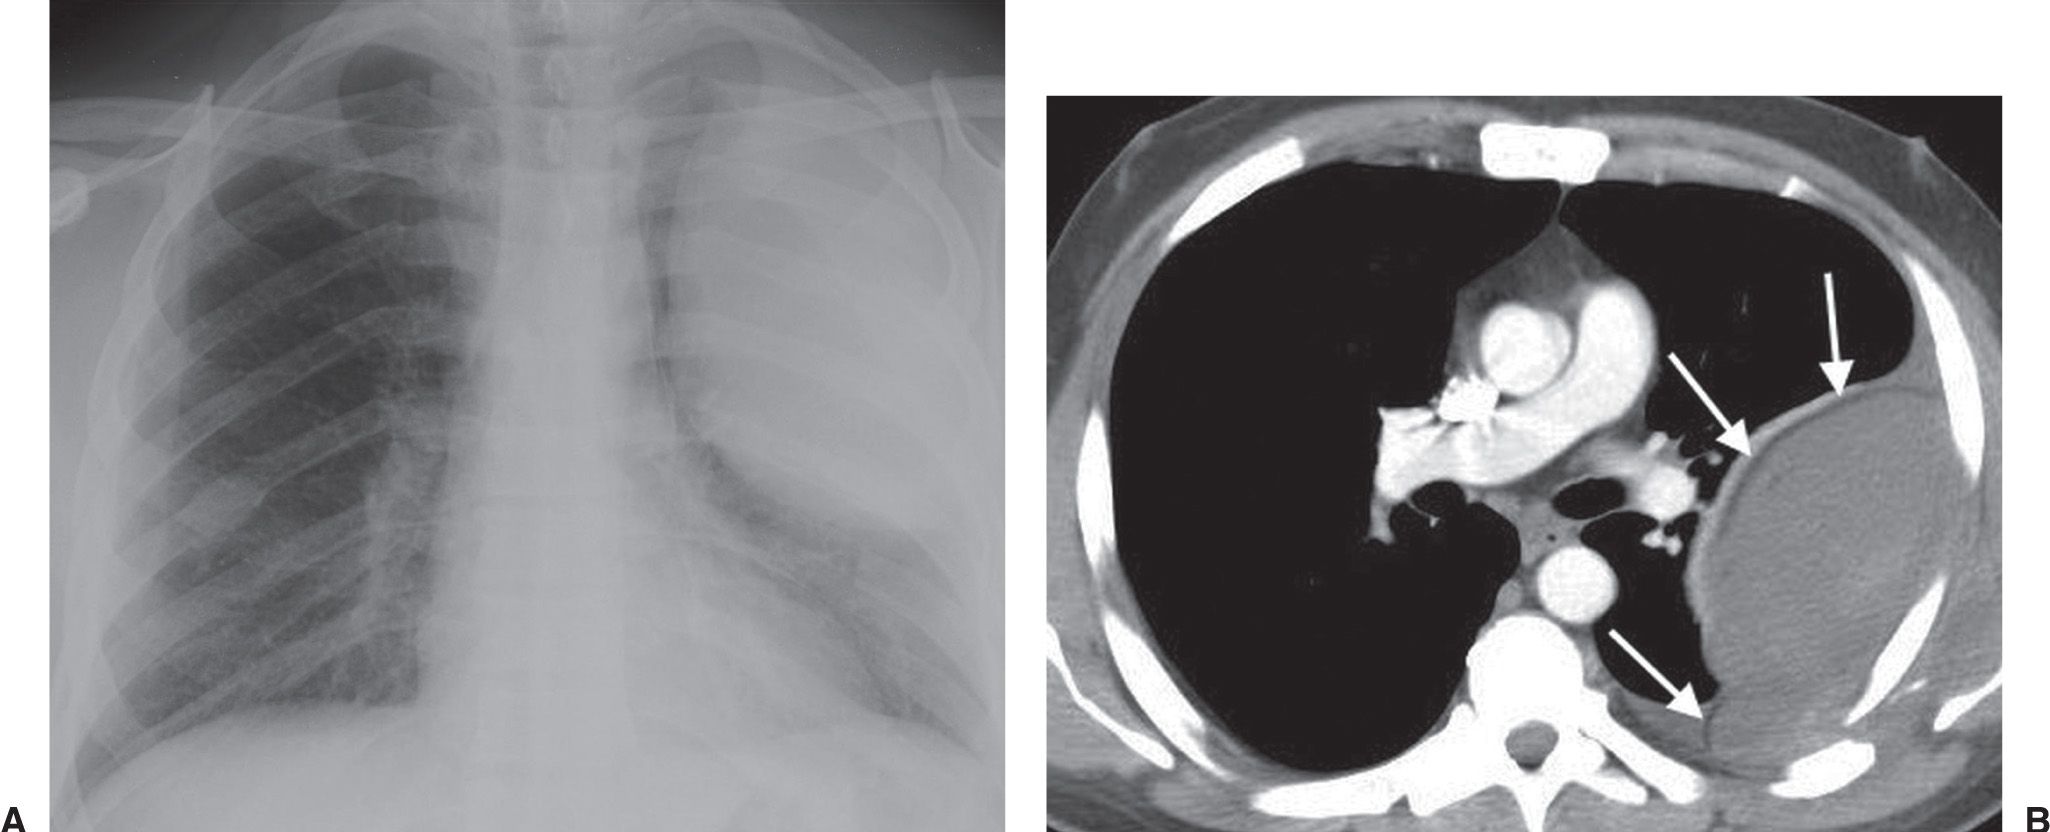

Pleural Effusion Radiology Key Pleural Tag Sign Radiology Pleural tags refer to slender bridges of soft tissue seen on ct scans that extend between masses in the lungs and the pleura. Juxtapleural lung nodules can be defined by their location within 15 mm of a pleural surface. Intrapulmonary lymph nodes are typically. Type 2 pleural tags on conventional ct images can increase the accuracy of early diagnosis of. Pleural Tag Sign Radiology.

Small right pleural effusion Image Pleural Tag Sign Radiology Pleural tags refer to slender bridges of soft tissue seen on ct scans that extend between masses in the lungs and the pleura. Juxtapleural lung nodules can be defined by their location within 15 mm of a pleural surface. Type 2 pleural tags on conventional ct images can increase the accuracy of early diagnosis of visceral pleural invasion by nsclc. Pleural Tag Sign Radiology.

Chest X Ray Interpretation pleural effusion Radiology Imaging Pleural Tag Sign Radiology Juxtapleural lung nodules can be defined by their location within 15 mm of a pleural surface. Pleural tags refer to slender bridges of soft tissue seen on ct scans that extend between masses in the lungs and the pleura. By univariate analysis and multivariable adjustment, surgical history, tumour marker (tm), number of pleural tags, length of solid contact and obstructive. Pleural Tag Sign Radiology.